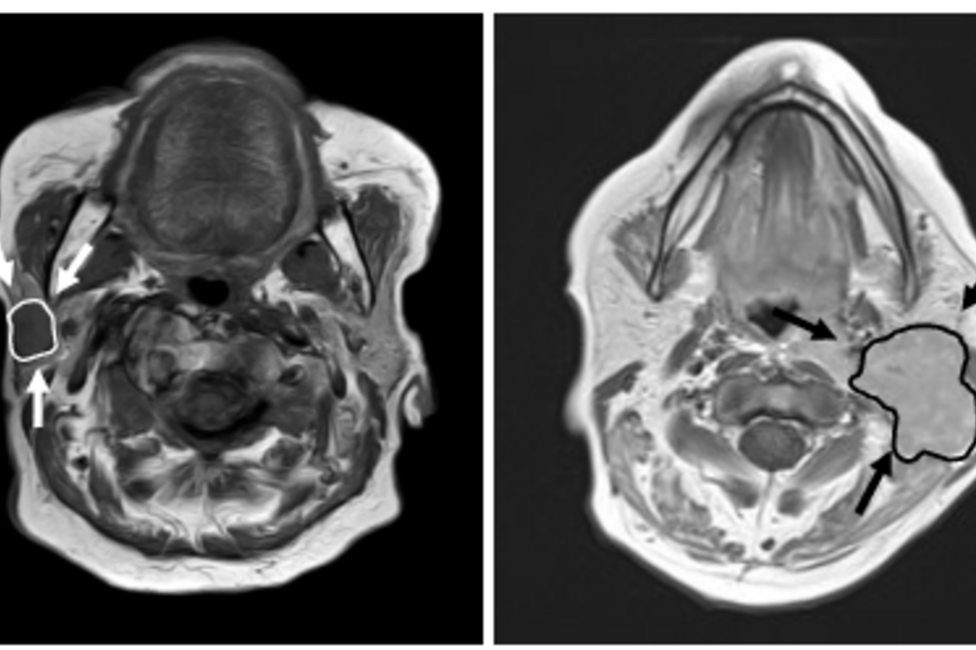

At the Department for Otorhinolaryngology 400 to 500 patients are diagnosed and (surgically) treated each week - amounting to tens of thousands of patients with various clinical pictures each year.